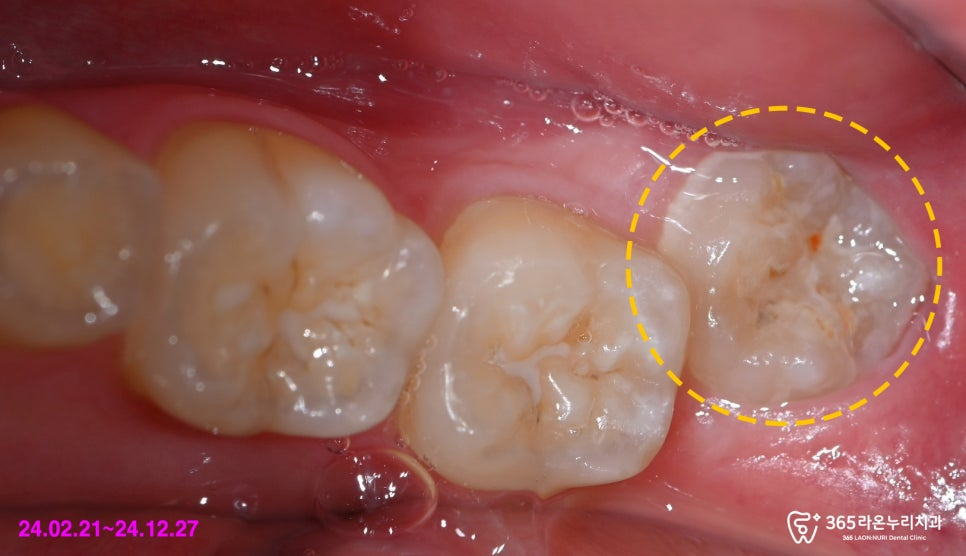

오른쪽 아래턱의 맨 뒤 사랑니가 관찰되는데,

해당 어금니 주변으로

잇몸이 많이 부어 있습니다.

우선 눈으로 해당 부위를 봤을 때,

치주 관리 부족으로 인한 부종 및

염증 소견을 발견할 수 있었습니다.

이는 정확한 명칭으로

‘지치주위염’이라 말씀드릴 수 있는데요.